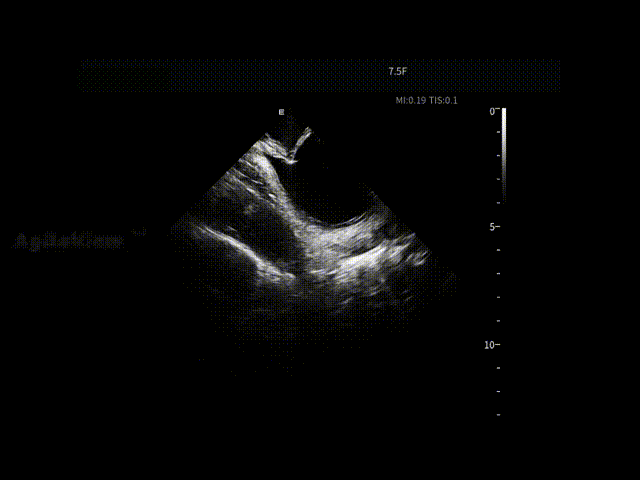

消融开始前,团队将ICE切换至PFA预设成像模式,以获得更贴合脉冲消融需求的术中影像。随着PulseSelect™ 脉冲消融导管逐步靠近肺静脉口及前庭区域,相关解剖边界在ICE下逐渐清晰呈现,为后续贴靠判断提供直观参考。

张曦教授将ICE导管置于右心房作为稳定观察点,在ICE实时影像引导下,PulseSelect™ 导管安全进入左心房,依次完成双侧肺静脉隔离,并进一步实施上腔静脉隔离。

在肺静脉隔离及左房后壁相关操作过程中,ICE持续显示消融导管与心房组织之间的空间关系与贴靠状态,使每一次能量释放都建立在明确的影像反馈之上,减少反复调整,提升操作连贯性。

房间隔穿刺

导管形变与贴靠-LA后壁

导管形变与贴靠-LIPV

导管形变与贴靠-LSPV

导管形变与贴靠-RIPV

导管形变与贴靠-RSPV

LPV口部消融

LPV前庭消融